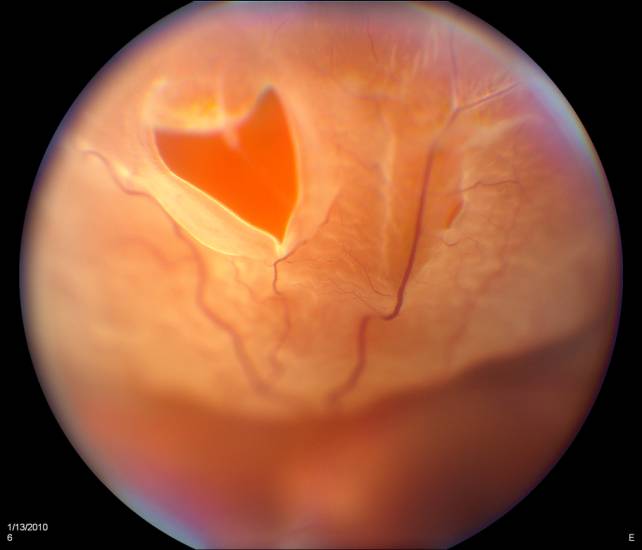

Фото

Диагностика